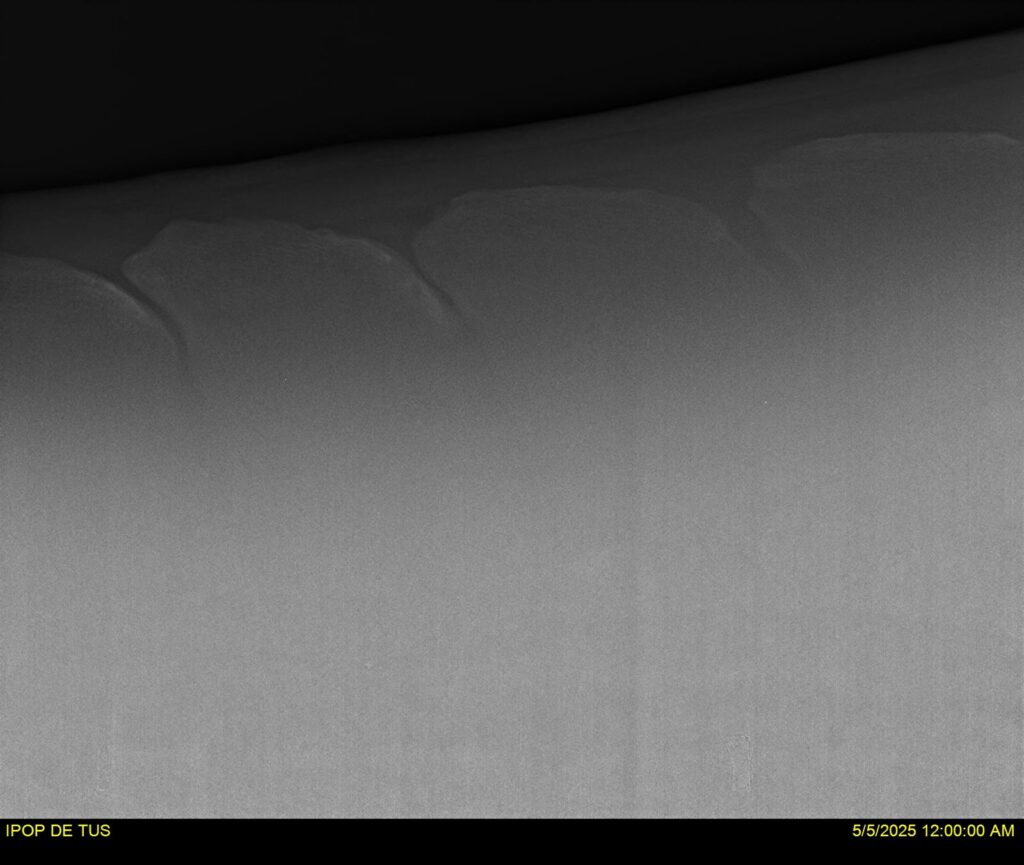

IPOP DE TUS, selle français, hongre, prendra 8 ans en 2026. LIFESTYLE x EROTICBLUS MONTOIS. Sans faute sur 125 et 130. Gentil cheval, respectueux avec des moyens et de la force. Transport OK, maréchalerie OK (pieds nus), santé RAS, Bilan clichés radios + clinique OK.

RADIOS ET CLINIQUE